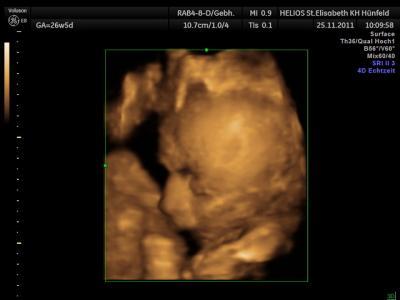

Bild zu Heute gehts mir gar nicht gut *wein* - Forum für Februar - Mamis